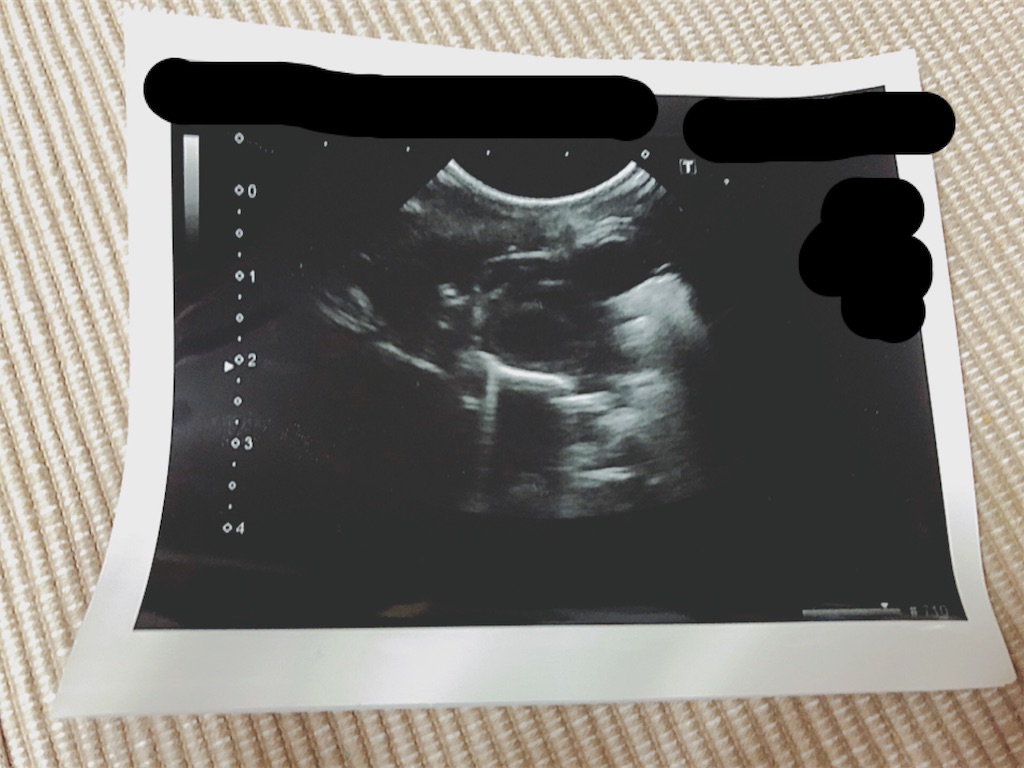

先生からいただいたエコーの写真。素人の私には何が何やらさっぱりわからぬ…